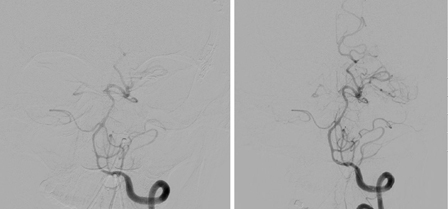

Endovascular techniques such as transluminal balloon angioplasty and intra-arterial vasodilators will reverse arterial narrowing, though clinical improvement is not consistent.[211][212]​ The American Heart Association/American Stroke Association (AHA/ASA) recommends that in patients with aSAH and severe vasospasm, cerebral angioplasty may be reasonable to reverse cerebral vasospasm and reduce the progression and severity of DCI.[37] There is some evidence to support early angioplasty (within 2 hours of symptom onset) in providing sustained clinical improvement.[213] Increased age and poor neurologic status at presentation are predictive of poor clinical outcome after angioplasty.[214] Enteral nimodipine, a calcium-channel antagonist, is given for vasospasm prophylaxis.[37] It reduces risk of poor outcome and secondary ischemia after aSAH.[215][216] [ Cochrane Clinical Answers logo ] ​ Despite their wide use, studies of corticosteroids in SAH have failed to show positive effects on DCI or overall outcome.[217] Tirilazad, a nonglucocorticoid 21 amino-steroid free-radical scavenger, was studied in several controlled trials for prevention of vasospasm. It was well tolerated but had inconsistent effect on overall outcome across the different studies.[218][219][220][221][222] [ Cochrane Clinical Answers logo ] ​ Studies have investigated the use of simvastatin and pravastatin in SAH with mixed results.[223][224][225][226]​ Routine use of statin therapy to improve outcomes is not recommended.[37] Studies investigating the use of antiplatelet agents in SAH, especially following endovascular coiling, have yielded conflicting results on the risk of DCI and overall outcome. Those conflicting findings, together with an increased risk of hemorrhagic complications, have resulted in less than universal adoption of this practice.[227][228] [ Cochrane Clinical Answers logo ] [Figure caption and citation for the preceding image starts]: Distal left vertebral and basilar arteries spasm before (left) and after (right) intra-arterial infusion of nicardipineCourtesy of Dr Salah Keyrouz; used with permission [Citation ends].Distal left vertebral and basilar arteries spasm before (left) and after (right) intra-arterial infusion of nicardipine